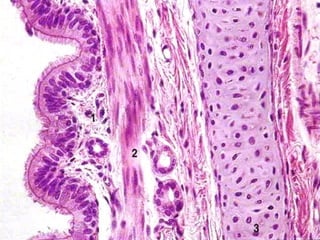

B R O N Q U I O S MUCOSA SUBMUCOSA CARTILAGO FIBROSA ADVENTICIA Epitelio respiratorio hasta epiteliosimple cilíndrico cccc Lámina propia tejido conectivo Fibras musculares lisas Tejido conectivo laxo Glándulas mucosas Vasos sanguíneos y linfáticos Placas irregulares de cartílago hialino y tejido fibroelástico Tejido conectivo laxo disminuye distalmente. I N T R A P U L M O N A R E S

B R O N Q U I O L O S MUCOSA Epitelio de simplecilíndrico cccc hasta cúbico con cilios sin células caliciformes, con células de Clara Tejido conectivo laxo Mas pliegues que en bronquios Músculo liso, relativamente más gruesa que en los bronquios Tejido conectivo laxo, muy fina hasta casi desaparecer en los bronquiolos terminales MUSCULAR ADVENTICIA